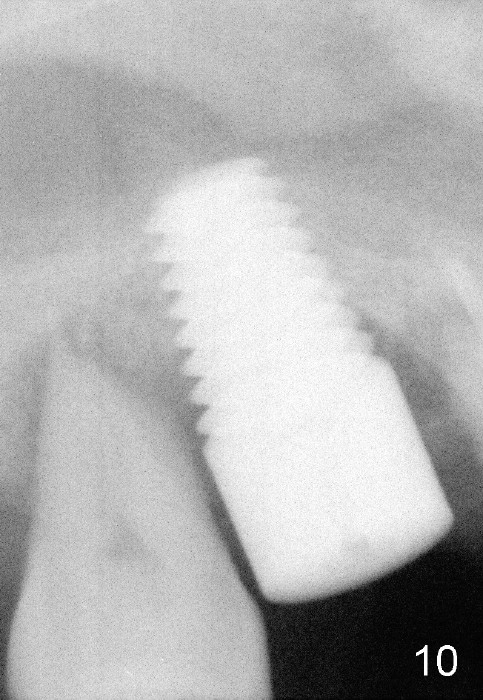

The 60-year-old man is a bruxer. All of the three upper right molars are nonsalvageable (Fig.1). Since #2 is symptomatic, it is planned to be extracted and restored first. As expected, there is severe alveolar destruction (single large socket), while the base bone is solid. A series of tapered osteotomes (2-5 mm) are used to create osteotomy in the base bone (gaining 4 mm into new bone), followed by 4.5x20 mm tap at the depth of 17 mm from the gingival margin (Fig.2). Then the depth is adjusted to 14 mm; the bone expansion and osteotomy continue until using 7 mm tap with good binding to the bone (Fig.3). A 7x14 mm implant is placed with insertion torque more than 60 Ncm (Fig.4). No bone graft is used for sinus lift considering sinus membrane perforation. The buccal flap is raised to reveal bony defect, which is covered by Osteogen (a synthetic bone graft) and then collagen membrane (Fig.6 *). Five days postop, the membrane undergoes a type of transformation (Fig.7 *) leading to a gingival tissue (Fig.8 *, 18 days postop). By 3 months, the gingiva has normal appearance (Fig.9), while the implant seems to be osteointegrated (Fig.10). Once the infected source is removed, our body has potential to regenerate.